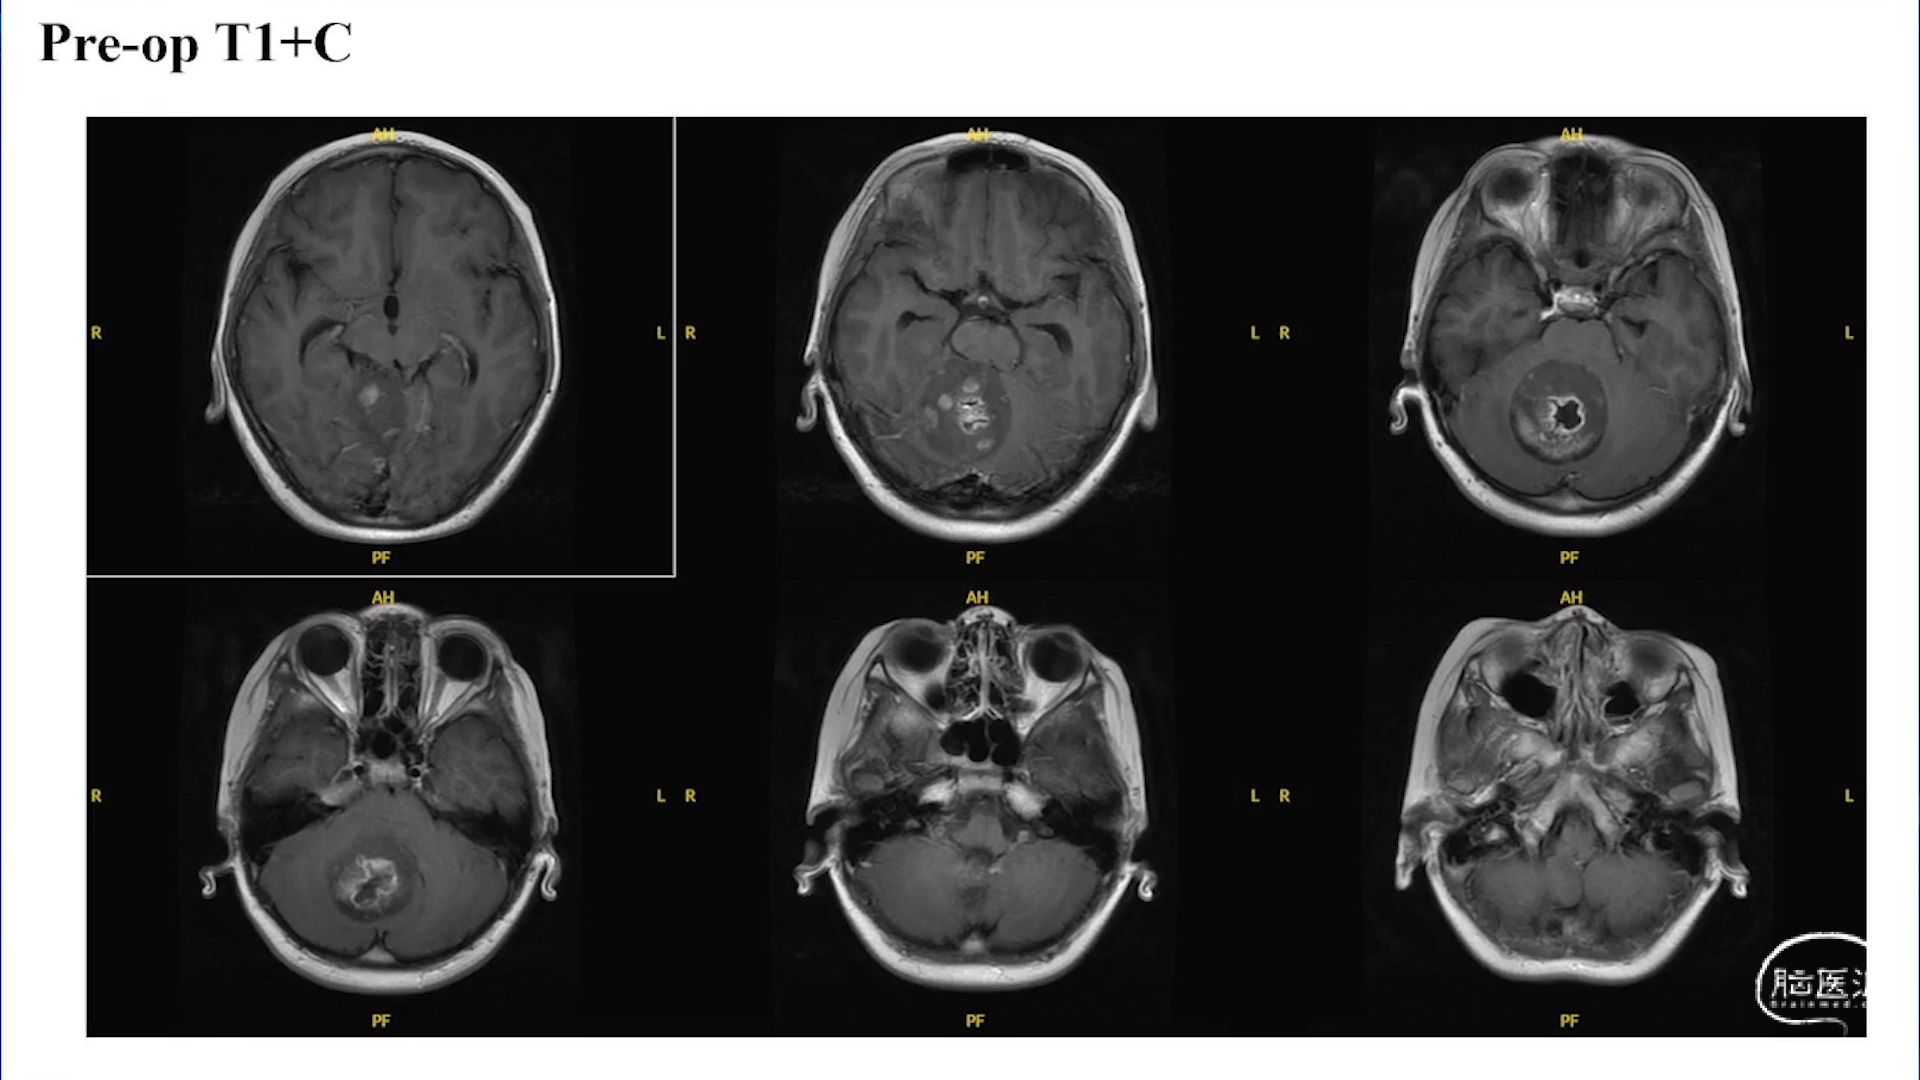

小脑星形细胞肿瘤